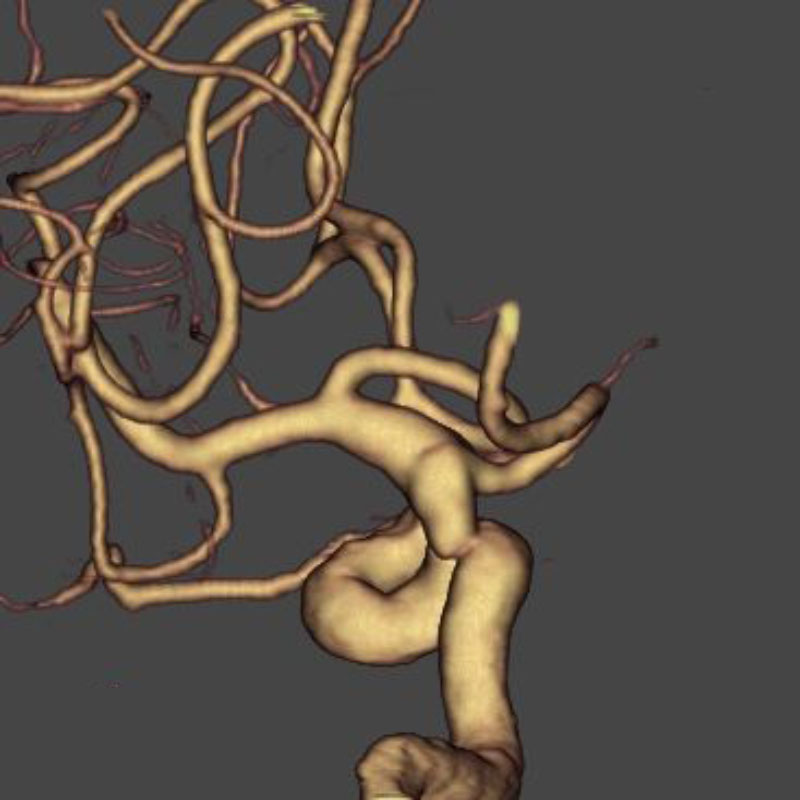

脳動静脈奇形

血管塞栓術

松田/濵田/元永